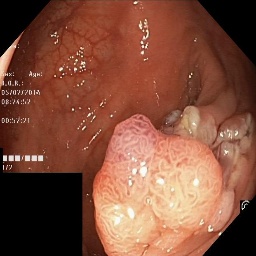

(a) Refer to caption Refer to caption Refer to caption Refer to caption Refer to caption Refer to caption

(b) Refer to caption Refer to caption Refer to caption Refer to caption Refer to caption Refer to caption

(c) Refer to caption Refer to caption Refer to caption Refer to caption Refer to caption Refer to caption

(d) Refer to caption Refer to caption Refer to caption Refer to caption Refer to caption Refer to caption

(e) Refer to caption Refer to caption Refer to caption Refer to caption Refer to caption Refer to caption

(f) Refer to caption Refer to caption Refer to caption Refer to caption Refer to caption Refer to caption

(g) Refer to caption Refer to caption Refer to caption Refer to caption Refer to caption Refer to caption

(h) Refer to caption Refer to caption Refer to caption Refer to caption Refer to caption Refer to caption

Figure 3: Sample data used and generated in the different steps of PolypConnect pipeline. (a) - real polyp images, (b) - manually annotated polyp masks, (c) - randomly selected colon images used as input to the final step of PolypConnect, (d) - extracted edge images of row c. (e) - extracted edge images of polyp regions of row a using the masks of row b. (f) - combined edge images of row d and f. (g) - generated polyp on the images of row c using EdgeConnect. (h) - generated samples from AOTGAN.